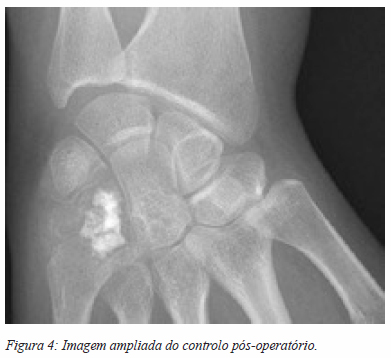

A hipótese diagnóstica, pela aparente não agressividade da lesão e dada a elevada prevalência, era a de um encondroma. Foi submetida a cirurgia de remoção da lesão. Por via dorsal, foi curetada a lesão com colocação de enxerto esponjoso de ilíaco e fosfato de cálcio. A recuperação decorreu sem intercorrências, com recuperação progressiva da mobilidade do punho. O controlo radiográfico da cirurgia está ilustrado nas figuras 3 e 4.